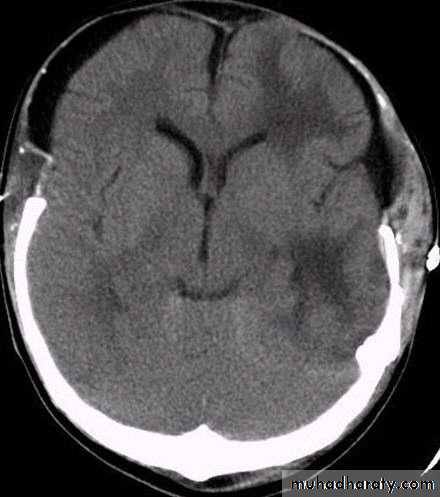

1. Brain Oedema (Cerebral Swelling)

Can be local (around a haematoma) or diffuse.

It is due to intracellular or extracellular accumulation of fluid.

It leads to raised intracranial pressure, which itself causes problems.

It is more common and more dangerous in children.